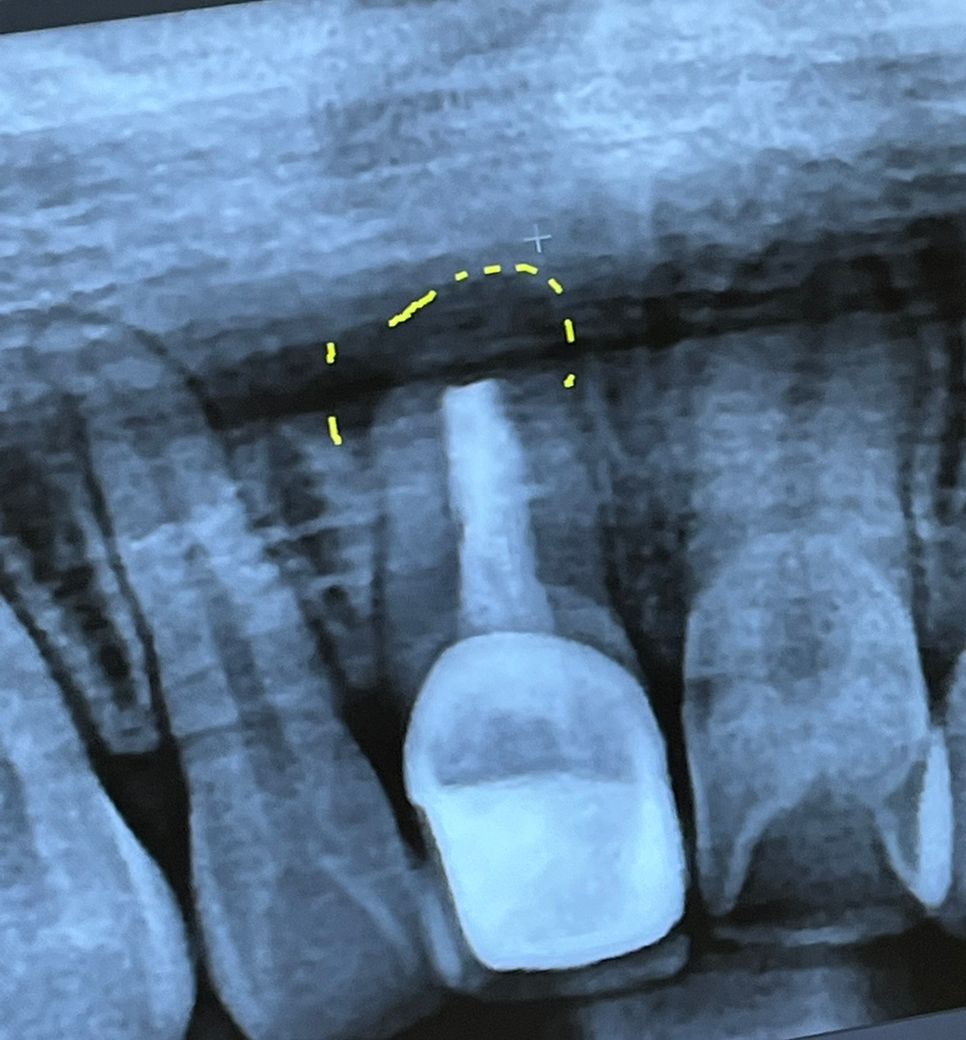

치아 뿌리 염증? 물혹? 씨티 좀 봐주세요ㅡ ㅜㅠ

처음엔 이정도 부위만 염증으로 보인다하셨어요

• 1번 째 사진